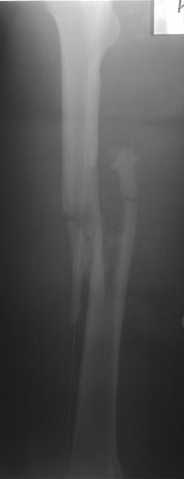

В приложении пример огнестрельного ранения бедра, оперированного на 2 сутки после ранения.

Единственно что наблюдал - замедленная консолидация, судя по серийным Рг граммам. В приведенном случае прии вялом мозолееобразовании сделал ошибку, решившись динамизировать гвоздь - перелом сросся со значительным укорочением бедра - повторная хирургия по удлинению бедра и проксимальным запиранием, больной мобилизован и вполне доволен(кстати заметить больной с ВИЧ инфекцией - изначально скомпрометированный иммунитет и несмотря на это, всё прошло без костной и мягкотканной инфекции.